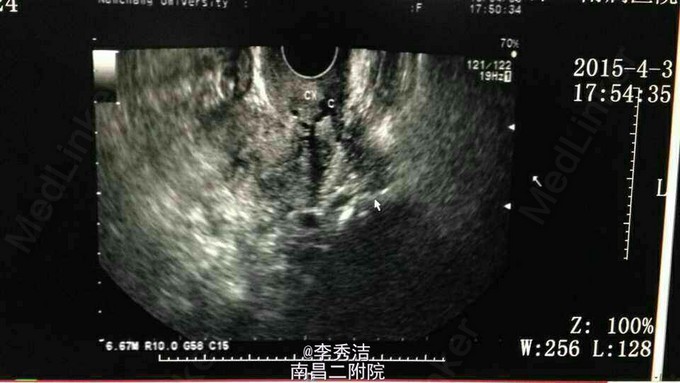

患者女,60岁,绝经10年余,发现血清 CA125升高10个月伴腰酸3个月。 妇检查发现左侧附件增厚,压痛明显。腹部彩超示肝右叶低回声结节。上腹部CT平扫示肝 S6段结节;左侧附件稍增大。血清 CA125 :511 CA125 。PETCT示左侧附件区结节装糖代谢异常增高灶,MT不除外。右侧肾上腺糖代异常增高占位,转移性MT首先考虑。右侧隔上、右侧盆腔糖代谢异常淋巴结。 行分段诊刮病理示:镜下粘液组织中见少于宫颈管粘膜,(子宫)镜下为粉染无结构物。抗炎一周后血清 CA125:1350.9 U/ml。后择期行腹腔镜探查术,术中探查:盆腔见少量血性分泌物,子宫表面散在芝麻大及绿豆大结节,双侧卵巢萎缩,形态正常,右侧输卵管形态正常,左侧输卵管壶腹部膨大增粗约1cm。决定行全子宫+双附件+左髂外增大的淋巴结切除术,术中冰冻切片示:(左侧输卵管)恶性肿瘤,上皮性癌, CA125 癌转移。术中进一步将盆腔淋巴结清扫干净,切除大网膜。外科医生探查肝肿瘤位于右肝脏面,切除之。术后石蜡切片病理报告示(左侧输卵管)浆液性乳头状腺癌。 患者于术后10天出院,后续进行化疗控制病情。